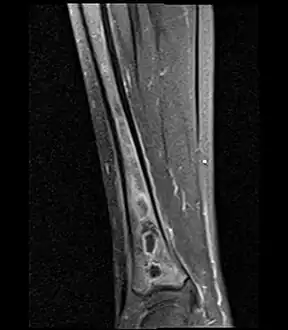

Fat saturated STIR (short tau inversion recovery) image showing hyperintense edema in the calf musculature, marrow edema, and subperiosteal pus. The intramedullary abscess cavity is hyperintense as well. -

Coronal fat suppressed STIR image showing, bone marrow and subcutaneous edema as well as subperiosteal edema. The thin hypointense rim surrounding the intramedullary collection represents the reactive interface between the abscess and the body's attempt to wall it off. -